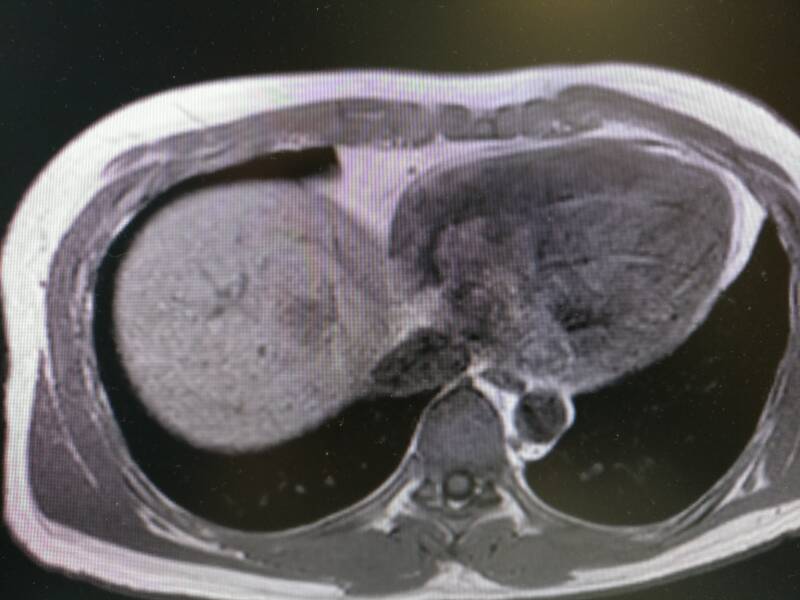

Het plaatje hierboven is een MRI-scan. Hierop kun je de weefsels veel duidelijker zien. Deze MRI is ongeveer dezelfde locatie als de twee bovenstaande plaatjes. Je ziet weer rechts het hart en links de lever. Mijn tumor ziet er nu donkergrijs uit in het lichtere grijs van de lever. In tegenstelling tot een CT-scan, waar die botten wit oplichten, zie je de botstructuur veel minder duidelijk op een MRI. Maar de spieren en de vetlagen onder mijn huid die op de MRI mooi zichtbaar zijn, zijn een grijze brij op de CT.

Als laatste nog twee plaatjes van de MRI scan. Hierop zie je de stappen waarmee de artsen door mijn lichaam kunnen scrollen. We gaan van boven naar onderen. Mijn lever wordt dus steeds groter op de plaatjes omdat die onderin mijn lichaam groter is.